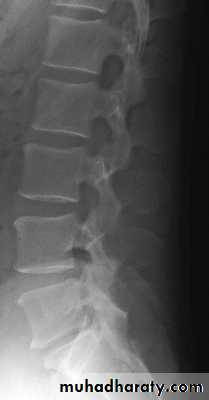

Lumbar Spine X Ray

Lateral radiograph

A/P radiograph• Sacrum